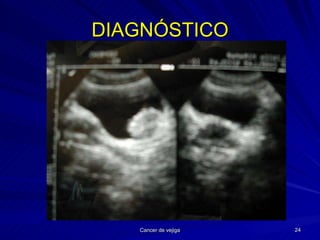

DIAGNÓSTICO Historia clínica Exploración física Palpar hipogastrio (masa, globo), FFRR TR Confirmar la hematuria Técnicas de imagen Endoscopia Citologías UIV Obligada para detectar otras localizaciones simultáneas (3-35 %)

DIAGNÓSTICO